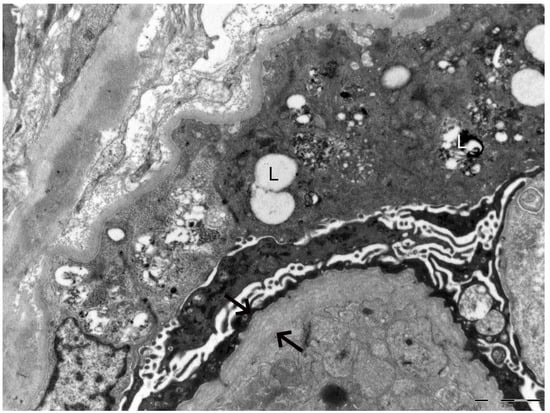

In 2025, owing to the unusually rapid loss of graft function (creatinine 3.89 mg/dL, eGFR 14 mL/min, urea 102 mg/dL, serum total proteins 56 g/L, AUCR 127 mg/g crea, proteinuria 0.81 g/die), the kidney biopsy performed on the native kidney in 2018 was re-evaluated at our center: a diagnosis of chronic interstitial nephritis with advanced glomerular sclerosis and severe arteriolar nephrosclerosis was established (Figure 1). On re-evaluation of the biopsy by electron microscopy, the residual glomerular capillary loops exhibited marked remodeling and multilamellation of the glomerular basement membrane, consistent with an Alport-like ultrastructural pattern. Podocytes contained abundant lipid droplets, autophagic vacuoles, and distorted myeloid bodies. Remnants of electron-dense deposits and areas of hyaline material were also seen. Numerous interstitial foam cells were present (Figure 2 and Figure 3).

Figure 2. Electron microscopy of the kidney biopsy. The arrows indicate marked remodeling and multilamellation of the glomerular basement membrane. The letter L highlights lipid droplets, autophagic vacuoles, and distorted myeloid bodies present within podocytes.

Figure 3. Electron microscopy of the kidney biopsy. The arrows indicate marked remodeling and multilamellation of the glomerular basement membrane.